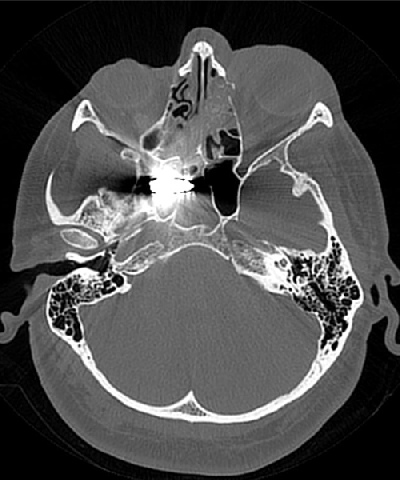

The injuries were of various types, including open craniocerebral trauma, amputated extremities, injured faces and thoracic-abdominal wounds with internal bleeding. The peculiarity of the soldiers was that they received bullet penetrating wounds through parts of the body not covered by body armor and helmet, for example, through the upper aperture of the chest, hot metal fragments up to 15-20 mm penetrated into the mediastinum and stuck to the wall of the main vessels or myocardium, which could only be removed in a specialized center.

Until the process of evacuation, both from them and to them, was settled, the wounded, the so-called 300, were being transported constantly day and night. These were critical injuries to the whole body, polytrauma, multiple foreign bodies in the neck near the vessels, and closed head injuries, hemopneumothorax, fractures of the ribs, shoulder blades, multiple fragmentation fractures of the pelvis, and avulsion fractures of the limbs, with long defects that often required amputation. Massive deformed soft tissue defects with multiple metal fragments from cluster munitions. Penetrating gunshot blind wounds of the abdominal cavity, liver and spleen ruptures with complicated internal bleeding, ureteral ruptures, post-traumatic aneurysms, damage to the pelvic organs and much more. Our military surgeons, anesthesiologists and everyone involved tried to save everyone at all stages of the evacuation, almost all of them already had experience in combat conditions since 2014.